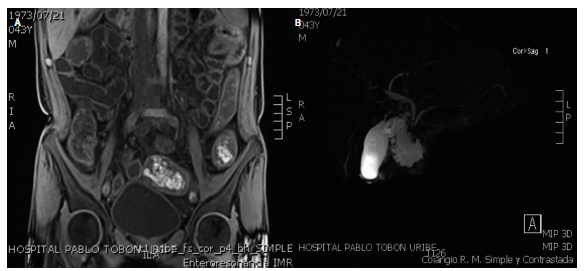

Se realizaron estudios endoscópicos en nuestra institución y se observaron lesiones que recuerdan pseudodivertículos (como en sacabocados) en el esófago distal (Figura 1A); mucosa gástrica de aspecto granular, apariencia de empedrado, principalmente en el cuerpo distal y el antro, con una úlcera inflamatoria en la región pilórica (Figura 1B) y formaciones pseudodiverticulares de aspecto inflamatorio crónico en el duodeno (Figura 1 C). La colonoscopia mostró una mucosa con una grave inflamación de todo el colon, con estenosis inflamatoria en la válvula ileocecal y múltiples úlceras inflamatorias en el íleon distal (Figura 1D-F). Se solicitó una enterorresonancia (entero-RMN) en la que se evidenció compromiso extenso de todo el intestino delgado por engrosamiento difuso, concéntrico, asimétrico e irregular desde el estómago hasta el recto (Figura 2A). Por la elevación de FA y GGT se realizó una colangio-RMN en la que se encontraron segmentos estenóticos lisos y cortos que alternan con segmentos de mayor calibre en la vía biliar intrahepática derecha e izquierda asociado con realce difuso de las paredes por un fenómeno inflamatorio inespecífico (Figura 2B). Las biopsias colónicas mostraron una mucosa ulcerada con distorsión de criptas, disminución de células caliciformes, infiltrado linfoplasmocitario en la lámina propia, exocitosis de polimorfonucleares y formación de microabscesos, Con tinción ZN, tinción ZN modificada, tinción de PAS (periodic Acid-Schiff) y citomegalovirus (CMV) negativos.

Figura 2 A. Entero-RMN: cambios inflamatorios dados por el engrosamiento difuso en todo el tracto digestivo. B. Colangiorresonancia en la que se evidencian estenosis cortas, lisas, con realce de la vía biliar intrahepática, hallazgos compatibles con CEP.